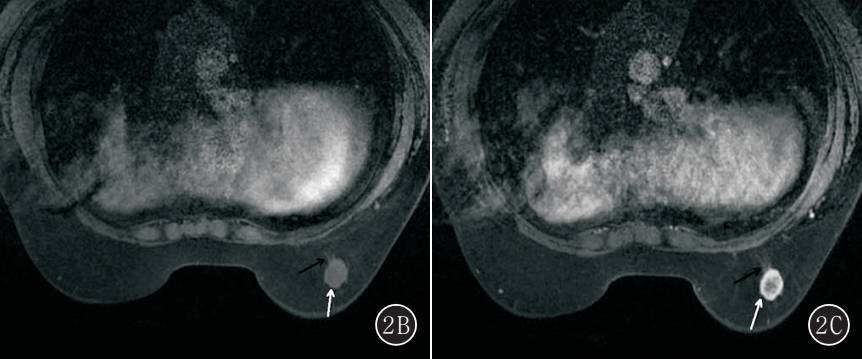

图2A~E 女,54 岁,右侧乳腺单纯型黏液腺癌。 A. T2 WI 右侧乳腺外下象限卵圆形肿块(白箭头),明显高信号,边缘多发细毛刺(黑箭头);B. T1 WI 平扫呈周边环形等信号,中心不均匀低信号(白箭头),边缘多发细毛刺(黑箭头);C. 动态增强呈环形强化(白箭头),强化环厚度不均匀,边缘多发细毛刺(黑箭头);D. 时间-信号强度曲线呈持续型;E. DWI 呈明显高信号(白箭头)